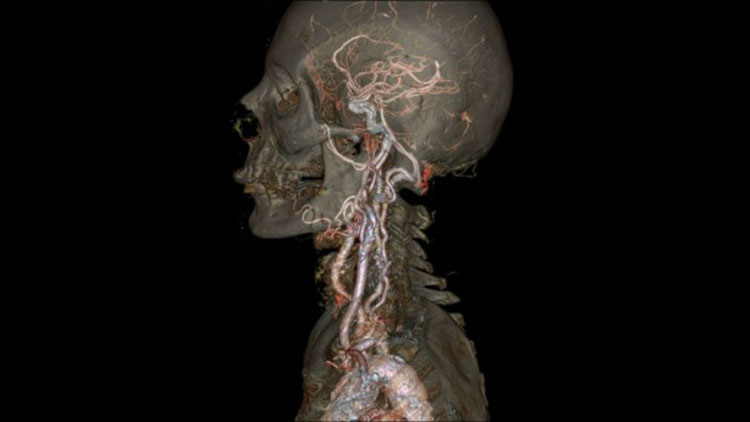

19. Una tomografía increíblemente precisa de la empresa Revolution CT.